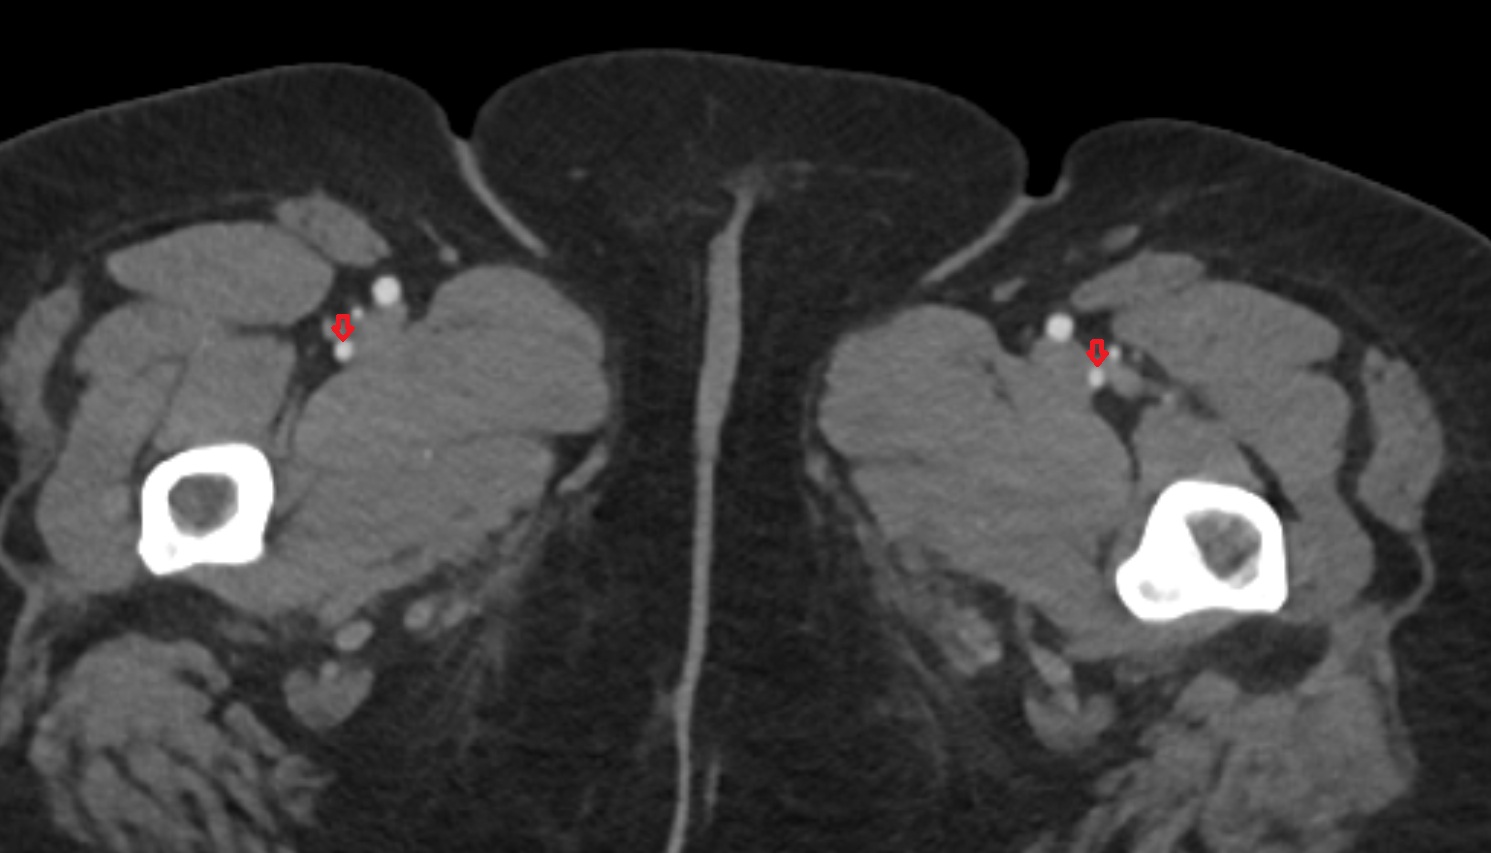

- Femoral artery

- Deep femoral artery (profunda femoris)

- Superficial femoral artery

- Deep femoral vein (profunda femoris vein)

- Medial circumflex femoral artery